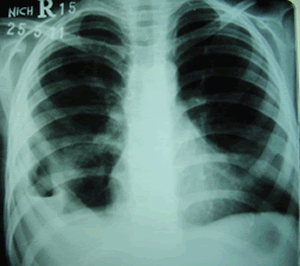

A 12-year-old girl presented with gradual onset of continuous, low to high grade fever, and cough which was initially non-productive but later productive of yellow sputum over 20 days. She had anorexia and lost weight. She developed respiratory distress which gradually worsened. Family history was significant for tuberculosis in grandmother who lived with her. She was unvaccinated. Initially they took treatment from a family physician but later referred to other facility where she was admitted and worked up as no improvement was noted. Her x-ray chest showed bilateral pleural effusions (Fig.1) and ultrasound of the chest revealed large effusions on both sides with thick internal echoes. At thoracocentesis, pus was aspirated from both the sides. She was started on anti-tuberculous treatment (Inj. streptomycin, isoniazid, rifampicin and pyrizinamide). After the thoracocentesis, her condition worsened and x-ray chest revealed left pneumo-thorax, (Fig.2) and she was referred to our centre.

Figure 1: Bilateral pleural effusions.